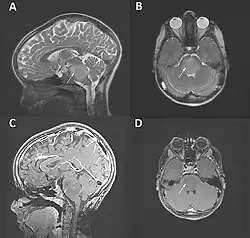

Das diffuse Mittelliniengliom, H3 K27-alteriert (DMG) ist ein bösartiger Hirntumor, der insbesondere im Kindesalter auftritt und im Hirnstamm, Thalamus und Rückenmark lokalisiert sein kann. Bei Auftreten im Pons wird es auch als diffuses intrinsisches Ponsgliom (DIPG) bezeichnet.

Der Tumor kann mittels Schnittbildgebung, vor allem der Magnetresonanztomographie, dargestellt werden. Der Tumor zeigt keine oder nur eine geringe Aufnahme von Gadolinium-Kontrastmittel.[5][8]